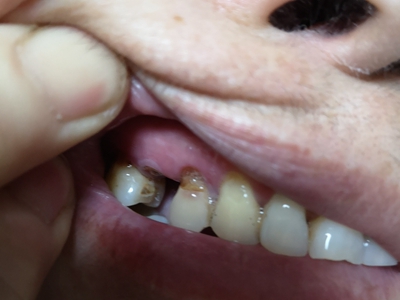

楔状缺损是一种非龋性牙颈部慢性损伤,是指发生在牙齿唇、颊面颈部的慢性硬组织缺损。典型缺损由两个夹面组成,口大底小,呈楔形。楔状缺损多发生于中老年人,主要原因是刷牙不当,防治措施是调整咬合关系,改善刷牙方法,配合相应的治疗。

楔状缺损与年龄相关,即年龄越大,缺损越重,患者多有横刷牙习惯,患牙为多颗甚至全口,常以口角附近的牙齿(尖牙、前磨牙)为重。典型表现为牙颈部缺损,呈楔形,由两个夹面组成,口大底小,缺损处质地坚硬,表面光滑,边缘整齐,无染色,轻微泛黄常为牙齿本色,严重时可导致牙髓腔暴露甚至牙齿横向折断,根据缺损深浅不同,可伴有牙齿敏感甚至疼痛。